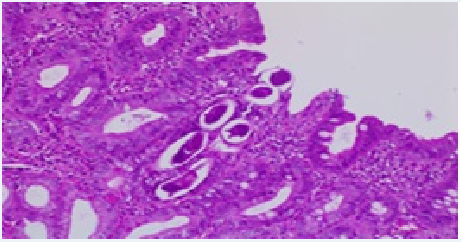

Histopathology revealed chronic duodenitis, eggs and adult forms of Strongyloides stercoralis, ulcerated chronic colitis in mild activity, with microabscesses of crypts and architectural glandular alterations. No signs of malignancy (Figures 3 & 4).

Figure 3 Histopathological examination of duodenal ulcers with chronic duodenitis, eggs end some adult forms of Strongyloides stercoralis, focis of ulceration and fibrino-leukocyte crust, without signs of malignancy - HE-200x.